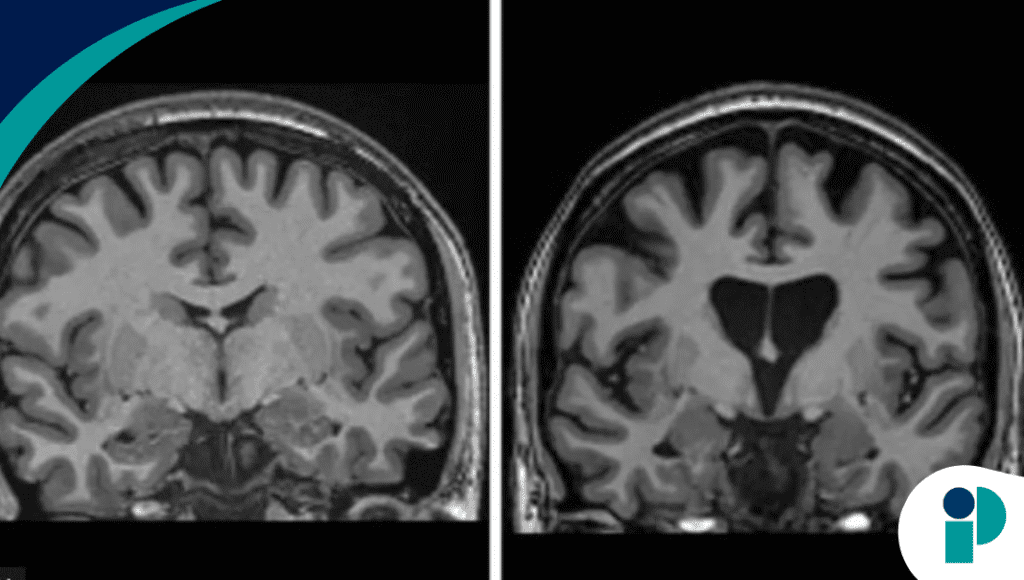

Los datos preliminares, difundidos por la biotecnológica uniQure, muestran no solo una ralentización clínica, sino también evidencia de que el tratamiento está salvando células cerebrales.